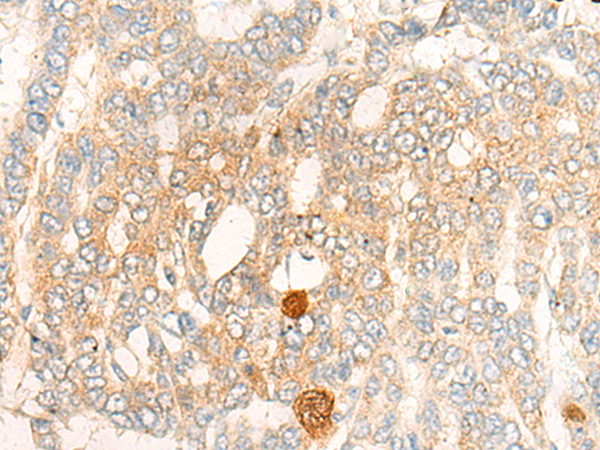

The image is immunohistochemistry of paraffin-embedded Human liver cancer tissue using 47021(DBT Antibody) at dilution 1/20. (Original magnification: ?00)